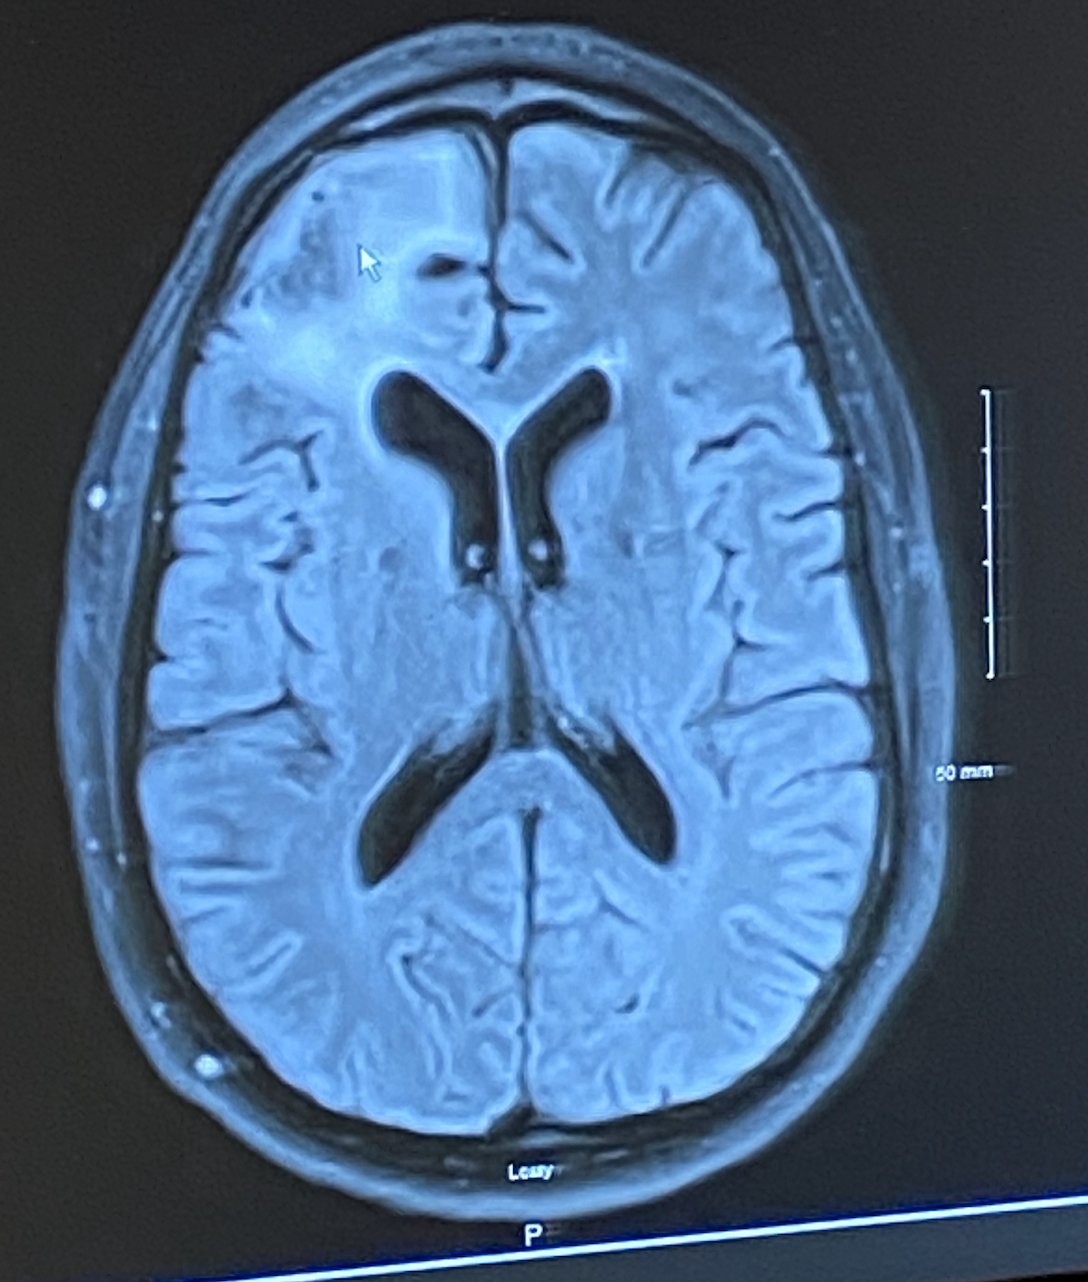

In December of 2020, Kevin had an MRI done of his brain to confirm that radiation was successful. While Kevin never really reacts or shows a tremendous amount of emotion, I was compensating for it in every way imaginable. Every time Kevin would forget something, not know an answer to something I thought he should, or even engage (or not engage) in a conversation the way I thought he should, I would panic. I would assume that even though the brain tumor was removed, that he and I were no longer compatible. I would assume that the tumor was back and it was aggressively growing. I would assume the absolute worst. I did it every time. The amount of angst and anxiety I had growing and leading up to that doctor’s appointment, was growing, and it was beginning to affect other people in our family.

We met that day with Dr. Ma and he confirmed that the brain tumor was in fact completely gone. He was beyond pleased with the way that Kevin had responded to radiation and that he was doing as well as he was (which led us to question how other people with the same type of radiation felt). With only a 10% chance of returning to the same spot, Kevin was technically “cured” and he was satisfied, but I was not. For me the percentage 10% in the medical world is high, for me it seemed unacceptable. I had about 10 additional questions about the other 10%, the plan then (no more radiation, only surgery), at what point the 10% decreased (it doesn’t), and then Dr. Ma looked at me and said “Sarah, focus on the 90%….. focus on the good in the situation.”